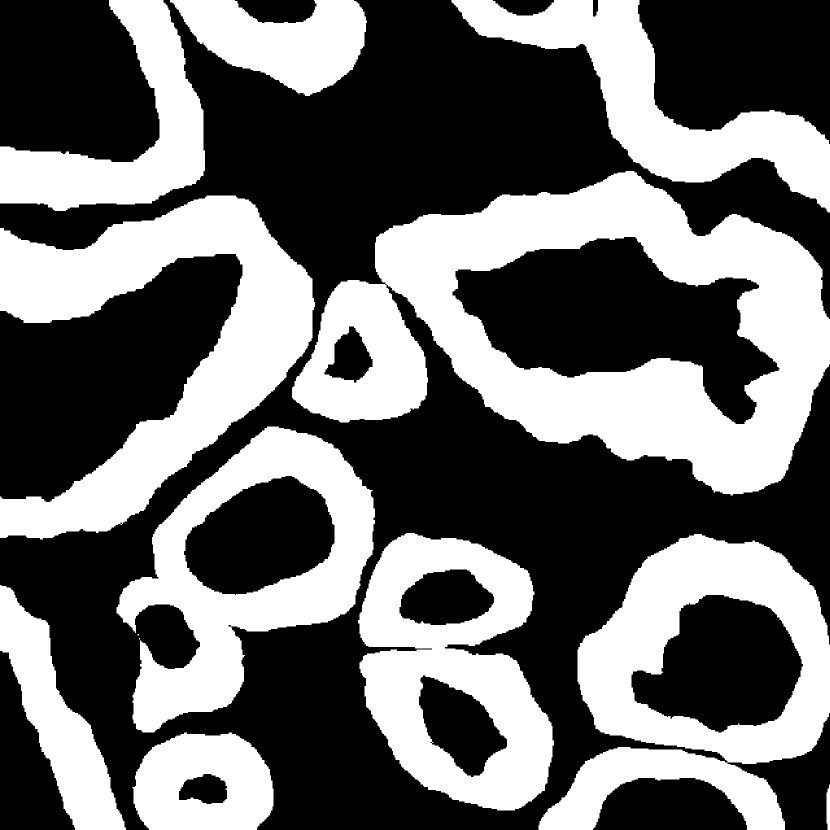

Fig. 3 shows two image examples, their ground-truth masks, and the final segmentations generated by competing models. Comparing with U-Net, Res-Seg based models generally have fewer false positives. Comparing with Res-Seg-Net, Res-Seg-Net and Res-Seg-Net both generate cleaner outputs, which can serve as an evidence that hierarchical refinings are effective in improving segmentations in both accuracy and robustness. These effects can be clearly seen within the areas highlighted with green boxes.

We fed Res-Seg-Net with the patch in the first row of Fig. 3, and output their segmentations maps of each layer in Fig. 4. The segmentation refining process is evident, as more and more details are added to the finer outputs. The low resolution segmentations tend to catch the primary shapes of the target objects. Moving upwards, they not only provide guidance for fine-resolution labelings to capture more details, but also set up certain guard to reduce the appearance of noisy spots.